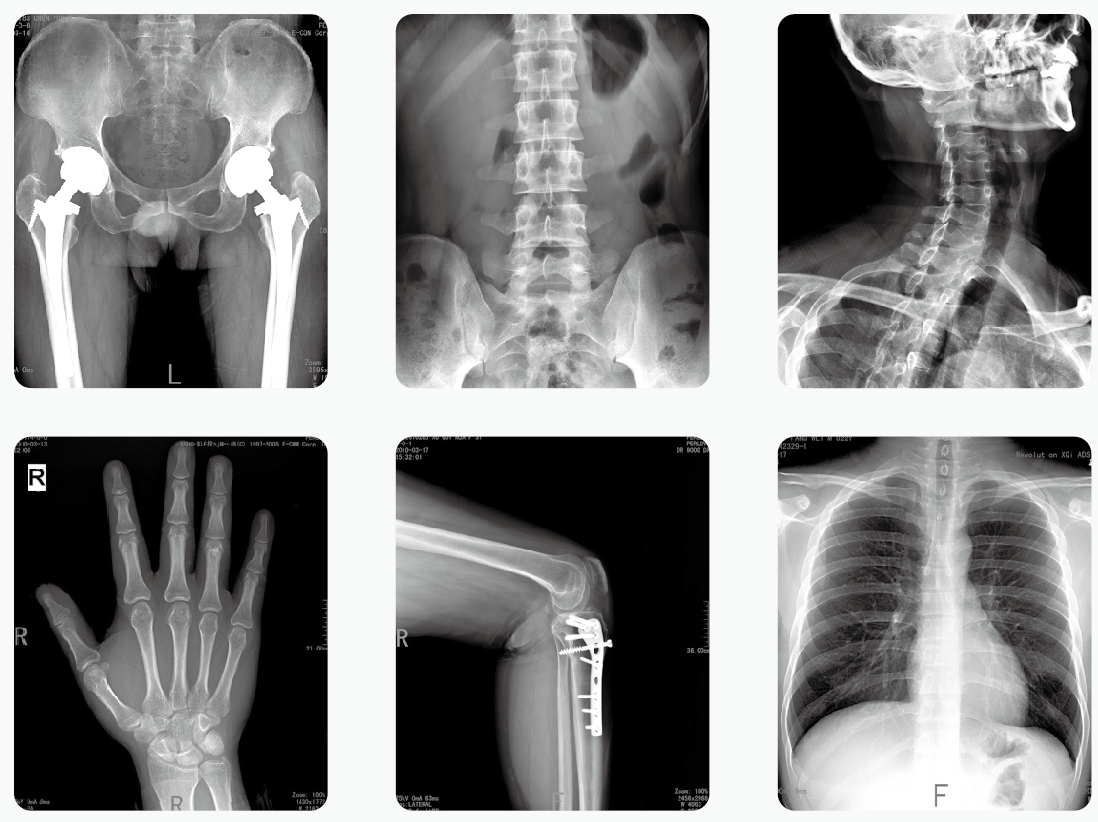

通過醫(yī)用X光機(jī)檢查,臨床醫(yī)生可以獲取病人很多重要的,甚至性命攸關(guān)的醫(yī)療信息,比如肺炎、骨折、腸梗阻等。這些普通X光檢查,對平常人而言就像是拍數(shù)碼照相,咔~可以了。但是對孕婦而言,有時的確是一個艱難的決策。那么,醫(yī)用X光機(jī)檢查,孕婦到底能不能做?

其實(shí),絕大部分醫(yī)用X光機(jī)檢查的部位都是四肢、頭、牙齒或者胸部,孕婦的生殖腺并沒有直接暴露在X光下。因此,在這些情況下,只要合理曝光及防護(hù),對胎兒是沒有危害和影響的。

但是,如果孕婦需要做腹部、盆腔、腰椎等醫(yī)用X光機(jī)檢查,此時胎兒是直接暴露在X光下的,這種情況就需要與醫(yī)生探討X光檢查的利弊后再做決定。